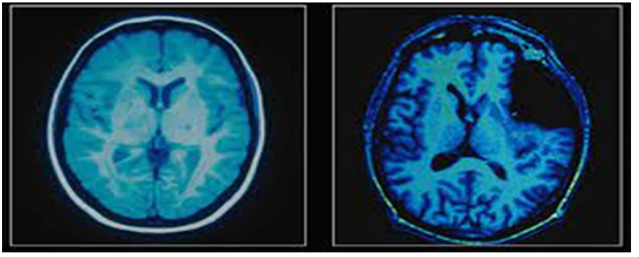

그 중 뇌과학자님의 강의를 흥미있게 들었는데 당시 아래와 같이 알츠하이머 치매 환자와 일반 정상인의 뇌를 촬영한 자기공명영상(MRI) 및 양전자 방출 단층 촬영(PET) 사진이 제 눈길을 끌었습니다.

<치매환자의 뇌와 일반 정상인의 뇌 비교 촬영 사진>

전문가가 아닌 사람이 보더라도 치매 환자의 뇌가 훨씬 위축되어 있고, 뇌실이 팽창되어 있는 사실을 바로 확인할 수 있었고, 강의 내용과는 무관하였지만, 이 사진을 본 후 관련 서적, 논문, 판례들을 찾아보면서 정신이상 범죄자들의 처벌에 대해 여러 가지 생각을 하게 되었습니다.